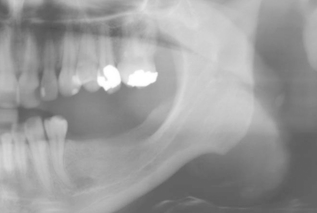

Unterkiefer – Mandibularkanal

Ein Standardbeispiel für die Notwendigkeit der dreidimensionalen Bildgebung ist der Unterkieferseitenzahnbereich. Ein am Panoramaröntgen in der Höhe suffizient scheinender Kieferkamm (Abb. 1) kann in der Breite unzureichend sein und so eine Implantation ohne vorherige Augmentation unmöglich machen. Das digitale Volumentomogramm offenbart den schmalen, spitzen Kieferkamm mit lingualem Unterschnitt, der N. alveolaris inferior lässt sich deutlich abgrenzen (Abb. 2). Somit ist vor der eigentlichen Implantation eine horizontale Augmentation des Implantatlagers notwendig. Bei einem Zweiteingriff nach der Einheilung des Augmentats ist die Implantation dann problemlos möglich (Abb. 3).